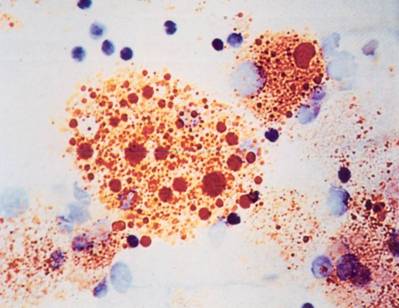

Κυψελιδική Πρωτεϊνωση

Λιποειδής Πνευμονία